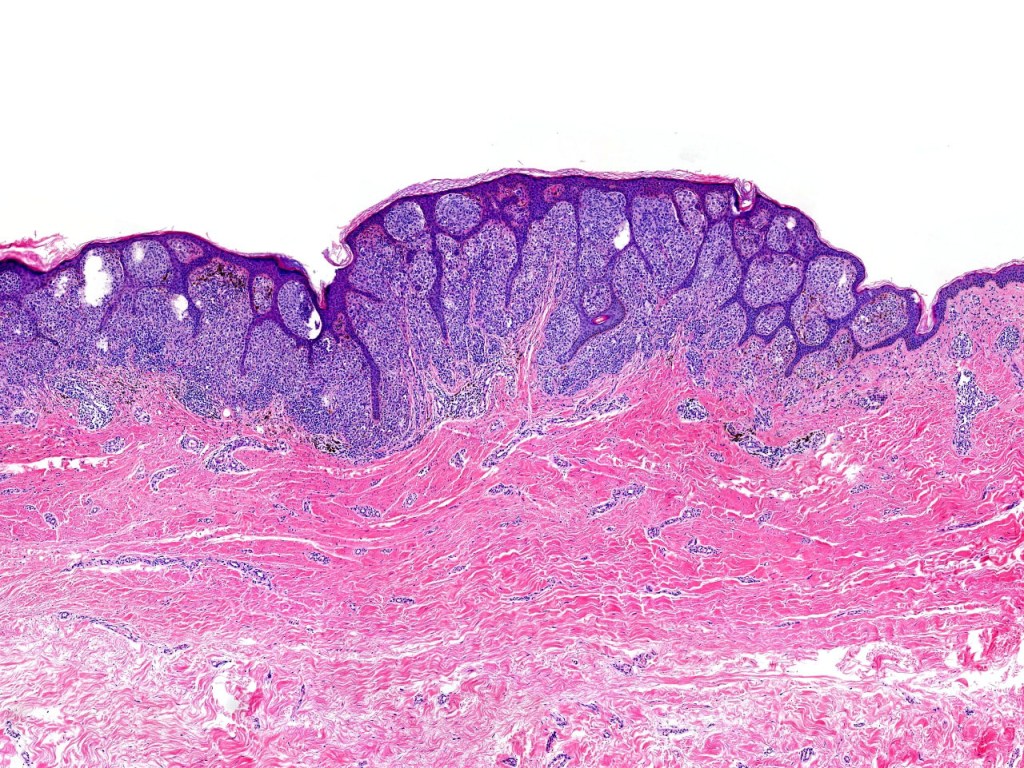

•Verrucous or dome-shaped, at low power, the lesion looks like a nevus

•Minimal or no junctional component

•Expansile nodules or diffuse

•Compression of connective tissue

•Stretched & elongated rete ridges in verrucous variants